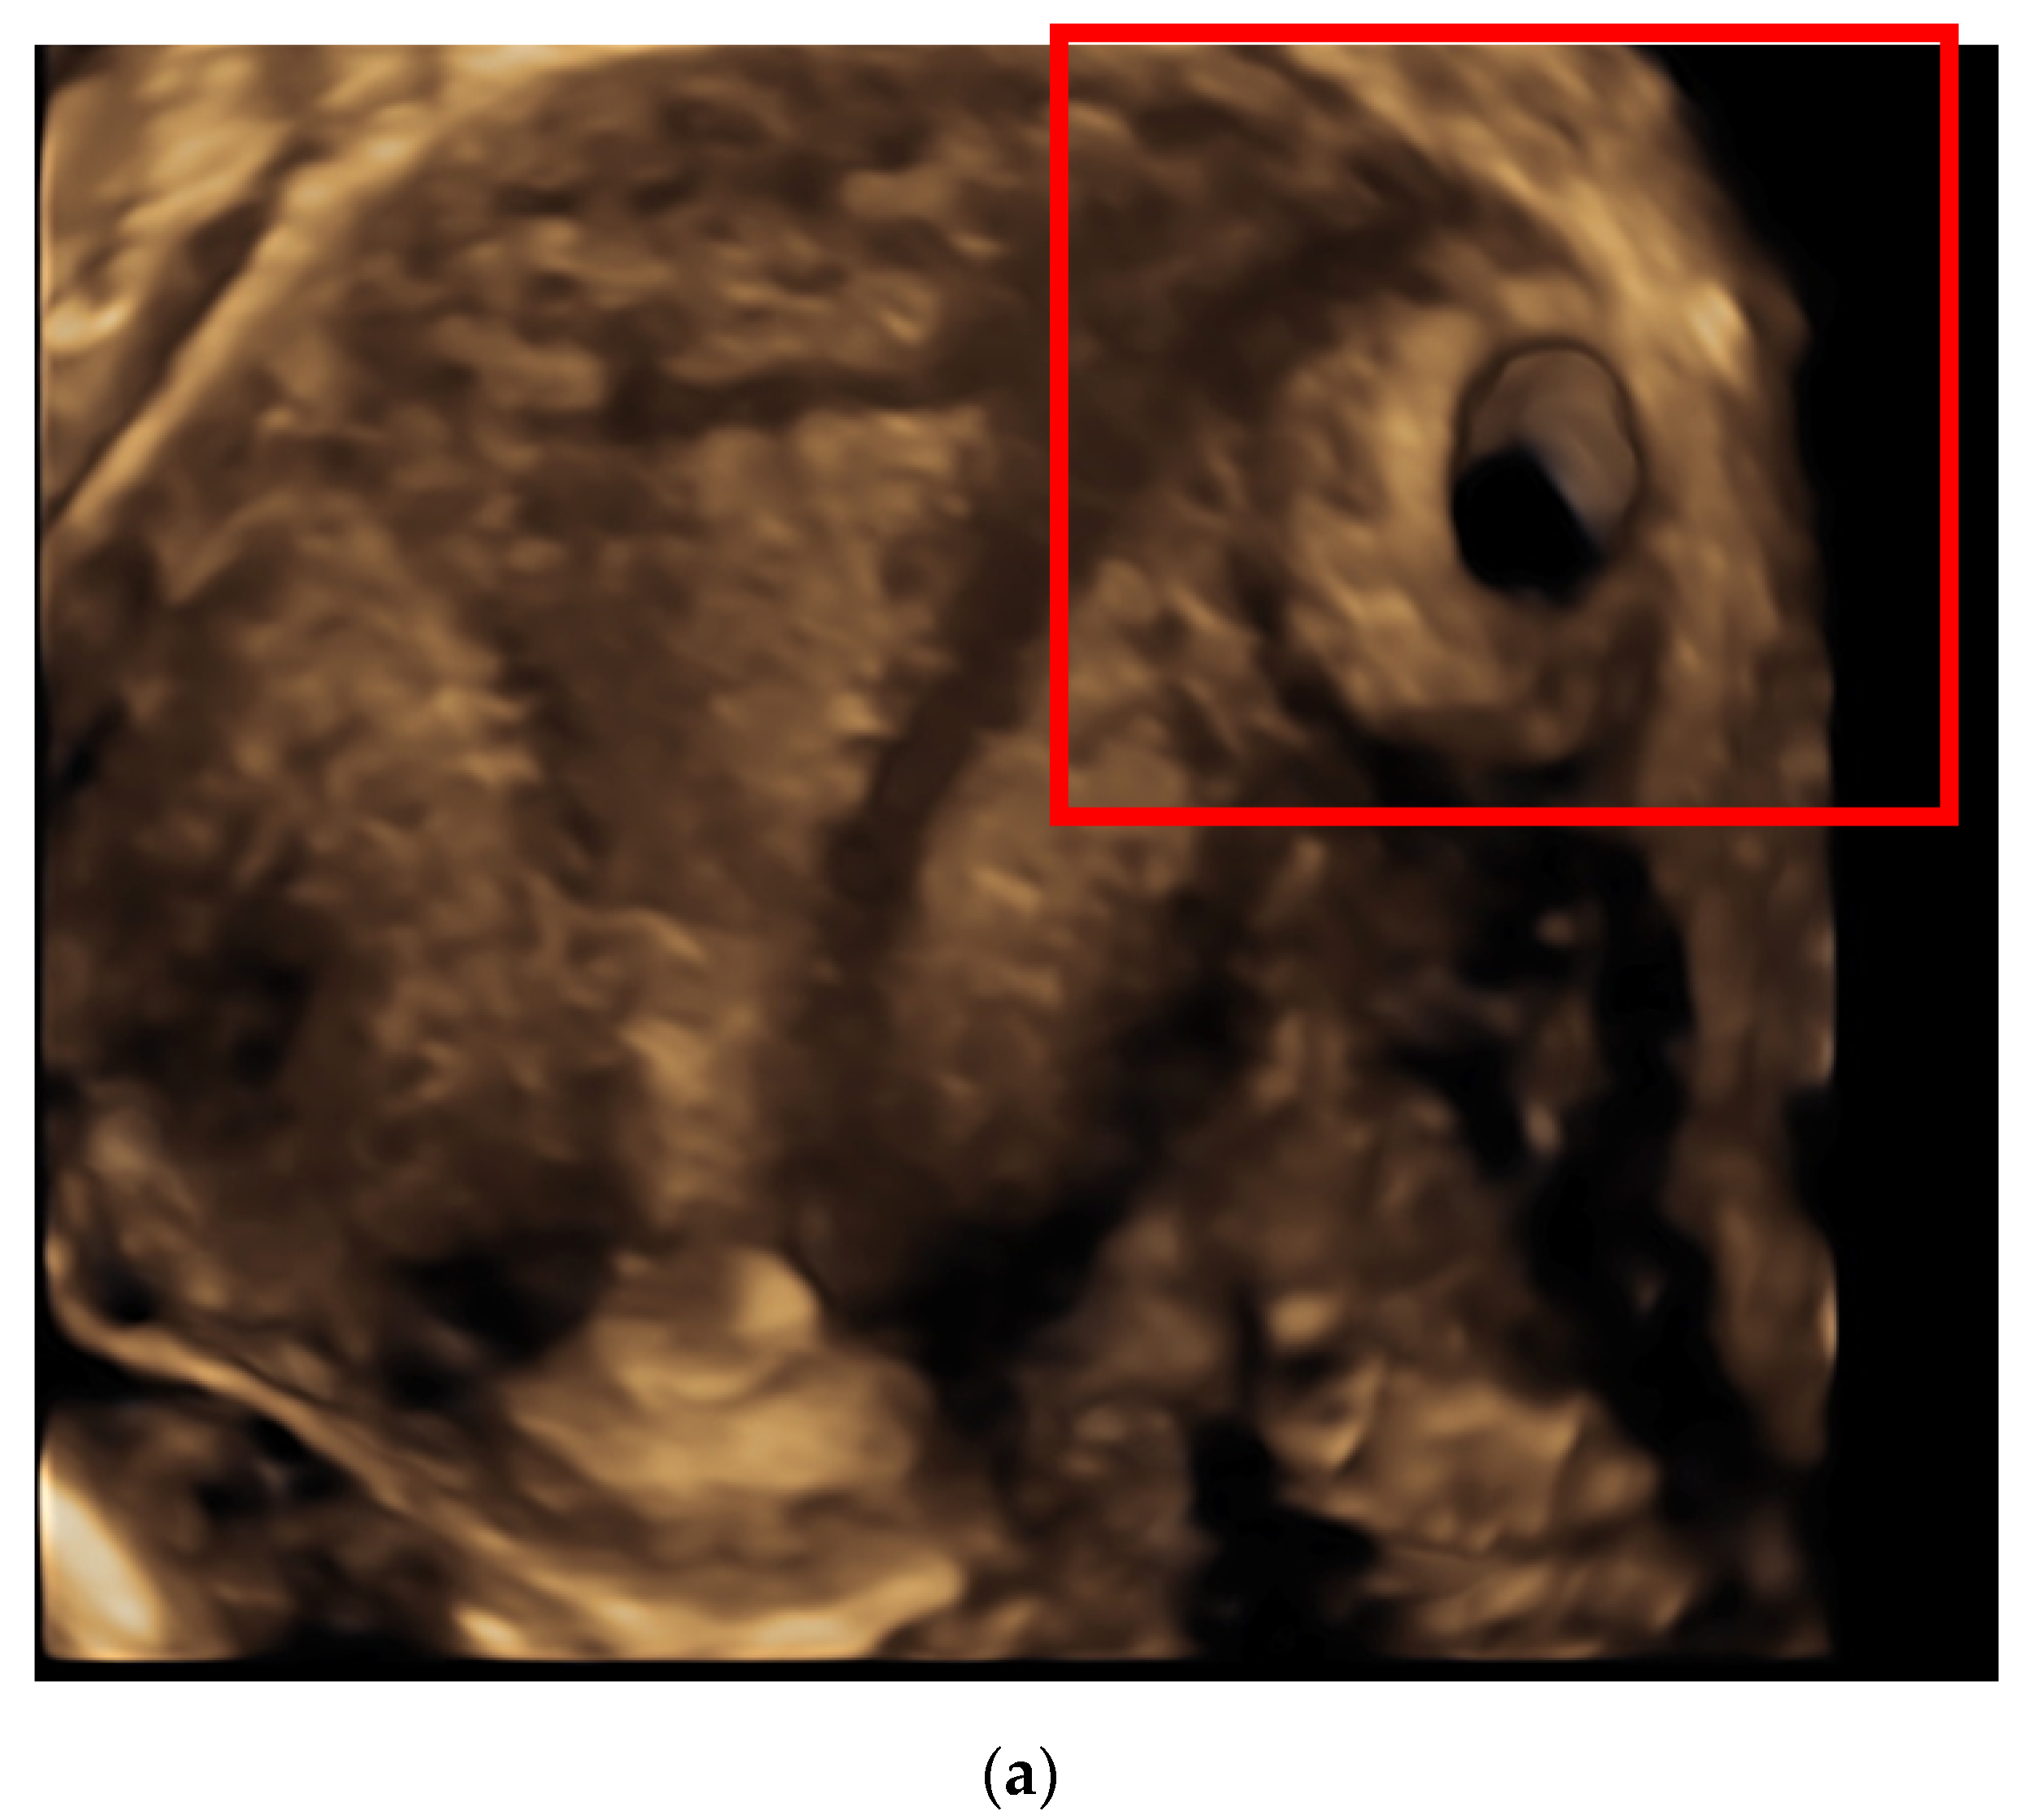

| Current Case | G2P0 (1 Previous EP treated by LPS: monolateral salpingectomy) | 7 weeks | 9 | + | 22,272 | Mifepristone 600 mg + MTX 1 mg/kg + 0. 1 mg folinic acid (four doses) |